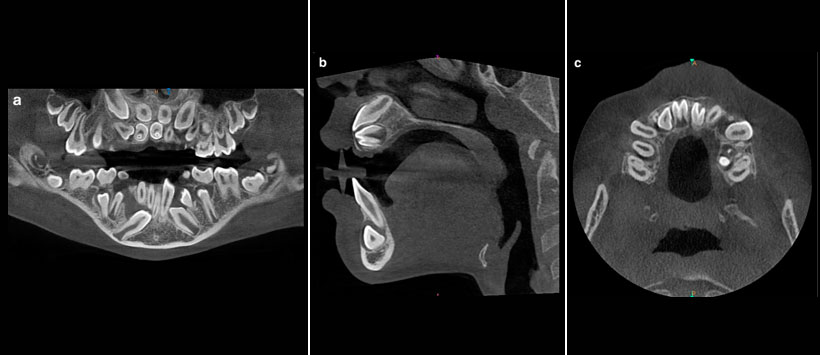

Los dientes invaginados (DI) puede reconocerse en casi todos los tipos de radiografías dentales, pero la ventaja del examen de tomografía computarizada con haz cónico (Figura 1 y Figura 2) es la evaluación del tipo de malformación. La siguiente clasificación ampliamente aceptada de DI fue propuesta por Oehlers :

Figura 1:  a) Ejemplo de invaginación coronal del incisivo lateral superior izquierdo. El esmalte en el diente 22 invagina el interior del diente, visto aquí como una línea opaca. una vista tangencial, b) Imagen de sección transversal. c) plano axial